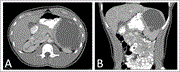

Unique multidisciplinary approach in a patient with small bowel obstruction and chronic mesenteric ischemia

Sally Tan and others

Journal of Surgical Case Reports, Volume 2023, Issue 10, October 2023, rjad577, https://doi.org/10.1093/jscr/rjad577